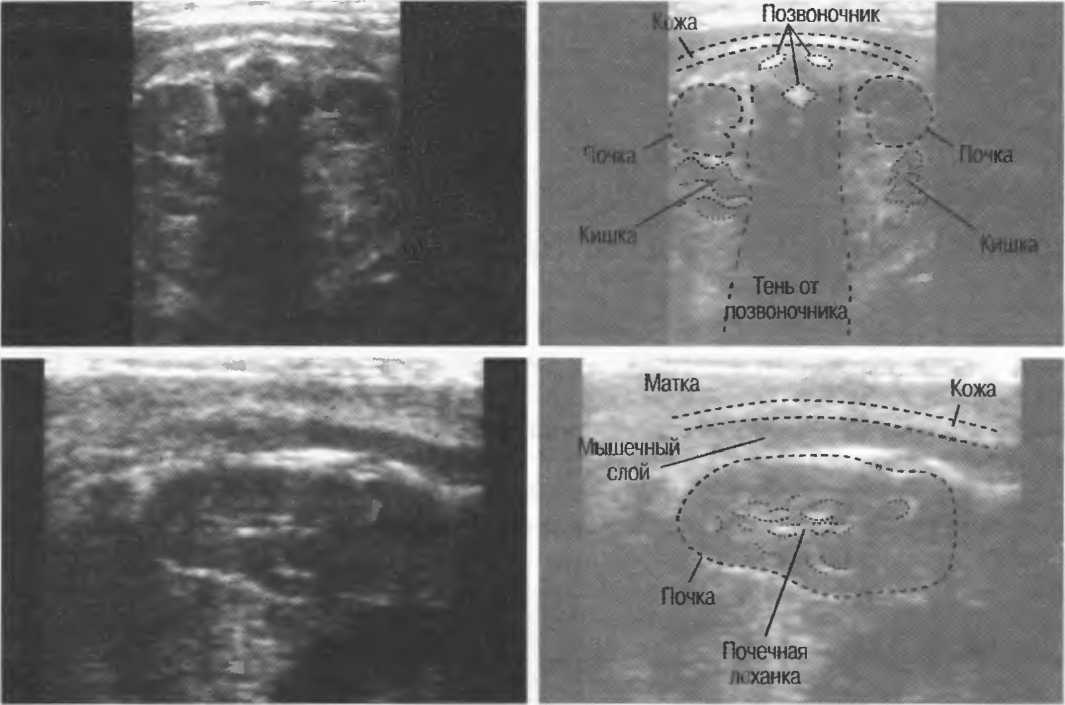

Рис.5. Два поперечных среза плода, демонстрирующих тень от позвоночника плода. Аналогичная тень от ребер может частично закрывать почки или печень. Изменяя угол наклона датчика, можно изменить положение тени таким образом, чтобы подлежащие ткани были видны отчетливо.